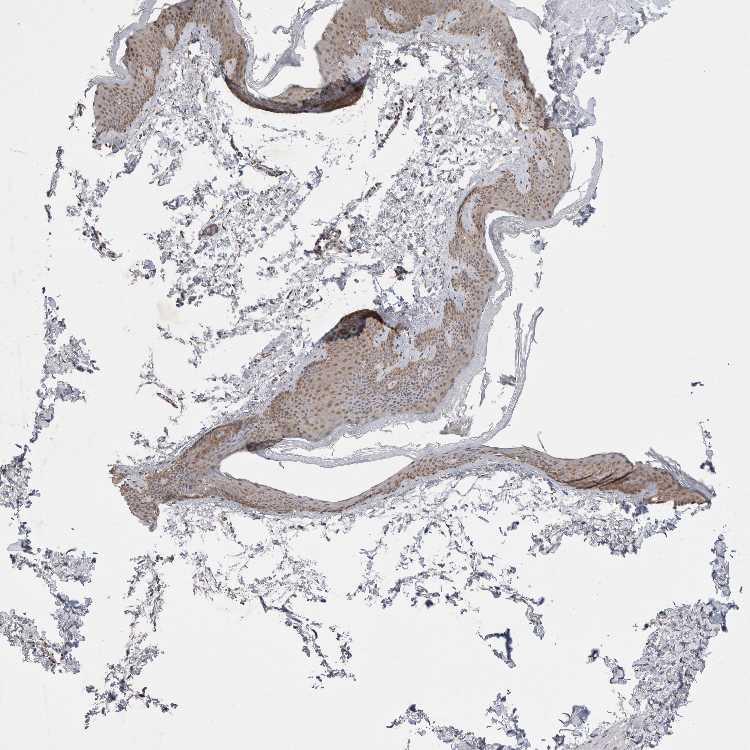

SKIN 1 - Antibody stainingi

Antibody staining in the annotated cell types in the current human tissue is reported as not detected, low, medium, or high, based on conventional immunohistochemistry profiling in selected tissues. This score is based on the combination of the staining intensity and fraction of stained cells.

Each image is clickable and will lead to virtual microscopy that enables deeper exploration of all samples and also displays staining intensity scores, fraction scores and subcellular localization as well as patient and tissue information for each sample.

Antibody HPA024000Antibody HPA024001Antibody HPA024467

Langerhans Not detectedMediumNot detected

Fibroblasts Not detectedMediumNot detected

Keratinocytes LowMediumLow

Melanocytes MediumMediumMedium

SKIN 2 - Antibody stainingi

Epidermal cells LowMediumMedium